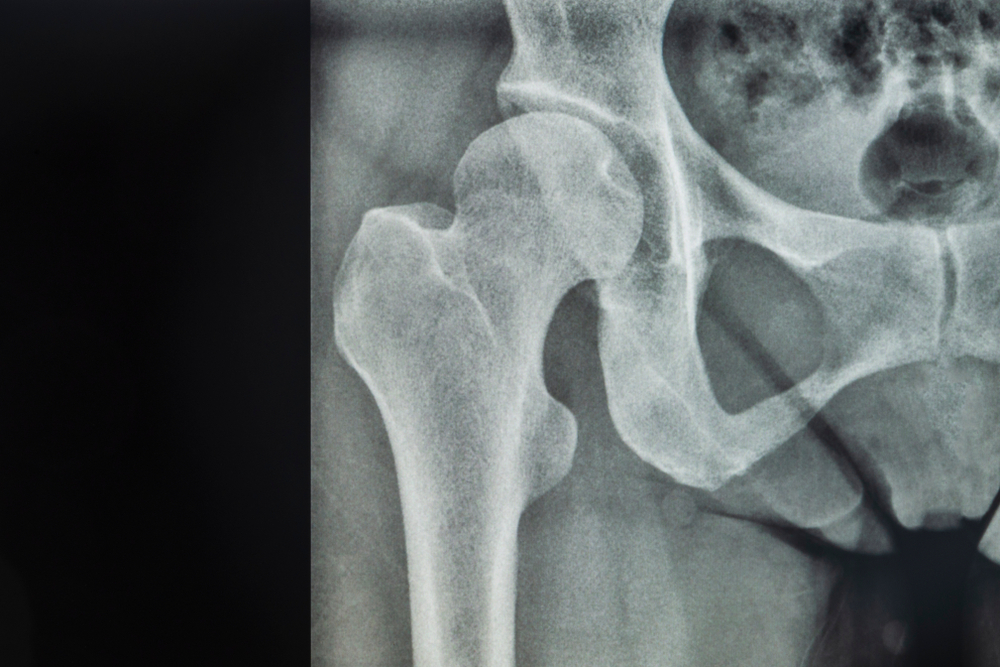

Osteoarthritis is characterized by the breakdown of cartilage in the joints, leading to pain, stiffness, and reduced joint mobility. The hips are commonly affected due to several factors:

4. Joint misalignment: Abnormalities in hip joint structure or alignment can contribute to increased stress on specific areas, hastening the onset of osteoarthritis.